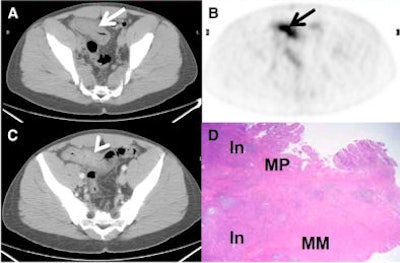

| 33-year-old male with Crohn's disease for three years, presenting with cramps after eating. Small-bowel series and CT scan showed marked thickening of distal ileum with luminal narrowing and proximal dilation of bowel. A PET/CT scan (A and B) revealed intense FDG uptake fusing to thickened ileum (arrows). SULmax was 13, and TIV was 258.2 SUL mL. Intravenous contrast-enhanced CT scan (C) shows mural stratification (arrowhead). In resected terminal ileum (D), there was acute and chronic transmural inflammation (In) and muscularis propria (MP) and muscularis mucosa (MM) hypertrophy and fibrosis. Image courtesy of the Journal of Nuclear Medicine. |